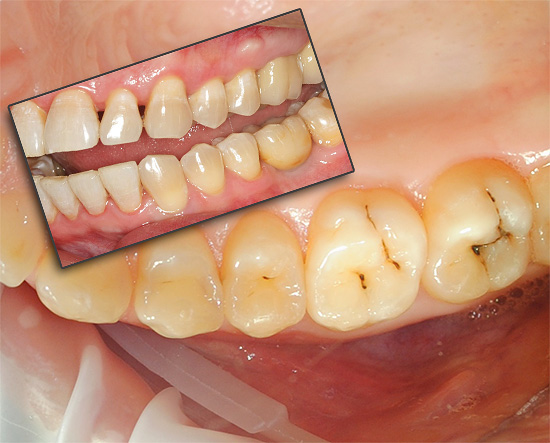

Quindi, cominciamo con il dolore, che sono segni caratteristici della carie. Già con le forme iniziali di carie, può apparire una sensazione di indolenzimento e una maggiore sensibilità dei fuochi di demineralizzazione dello smalto (cioè aree di smalto con componenti minerali parzialmente lavati). In questa fase, per prevenire un'ulteriore distruzione dei tessuti duri, è necessario prendere un ciclo di terapia rimineralizzante il più presto possibile (almeno, utilizzare dentifrici rimineralizzanti).

Tuttavia, il dolore severo può apparire solo quando la distruzione cariata raggiunge il confine smalto-dentina - in questo caso, i tessuti dei denti sono sensibili a varie sostanze irritanti (freddo, dolce, ecc.). In tali situazioni, per sbarazzarsi rapidamente delle sensazioni spiacevoli, è sufficiente eliminare semplicemente l'irritante e il dolore passerà immediatamente. Tuttavia, ovviamente, per un trattamento completo senza sigillo non sarà più sufficiente.

Il dolore nella carie media e profonda si verifica a causa del fatto che lo strato di dentina è penetrato da molti tubuli dentinali che alimentano il dente e ne determinano la sensibilità (e hanno anche una certa connessione con il "nervo" dentale). Quando lo strato di dentina viene distrutto, appare qualcosa come una "ferita" di dentina, che risponde all'azione degli stimoli.